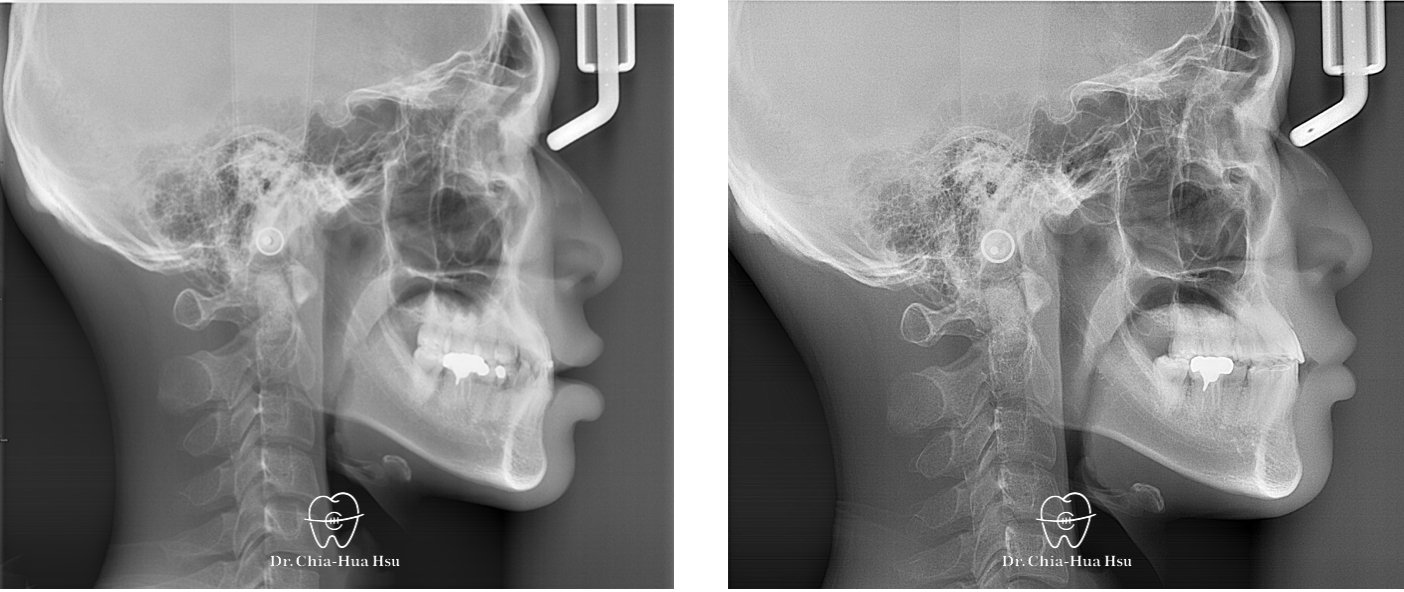

困難案例、先天性缺牙、錯咬、齒間縫隙

成人矯正 | 金屬矯正 | 非拔牙治療

• 這位醫學系學生因為牙齒不整齊前來求診,諮詢後患者才知道原來他有先天缺牙的問題,由於患者不想植太多牙,和患者討論後決定試試看把牙齒縫隙都盡量關起來。在許醫師的悉心治療下,以最省錢的方式順利讓患者牙齒恢復美觀、重建自信!

• 病患主訴:在意門牙牙縫和齒列不正。

• 問題分析:患者除了門牙牙縫、齒列不正問題,有先天性缺失上顎雙側側門牙兩顆以及左下第二小臼齒,並且左下方有滯留的乳臼齒,治療難度高。

• 治療方式:使用傳統金屬矯正器,並搭配拉口內橡皮筋的方式來讓上顎後排牙齒往前移動,以關閉缺牙縫隙。

• 治療時間:2 年 4 個月。

• 治療結果:改善缺牙、縫隙,以及上下顎咬合關係,左下乳臼齒拔除後以一顆植牙重建。